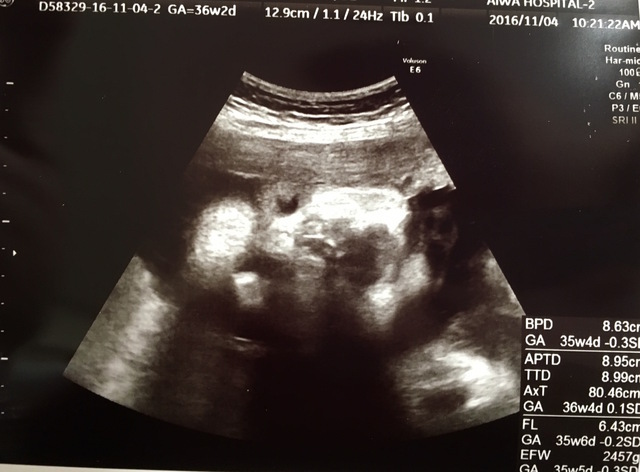

36週1日(36w1d・男の子)|トーママ さん(28歳)

エコー写真撮影時のエピソード:

標準よりも少し大きめに成長していた息子。 エコー写真をもらうたびに主人にラインで送ってました。

大体いつもよくわからんねとか言ってた主人ですが、この写真を送ると速攻返信が… 完全にあなたの血を引き継いでるねと。

自覚はしていませんが、私がアヒル口みたいで、それのことを言われました… 姉に送っても言われ、友達に送っても言われました。